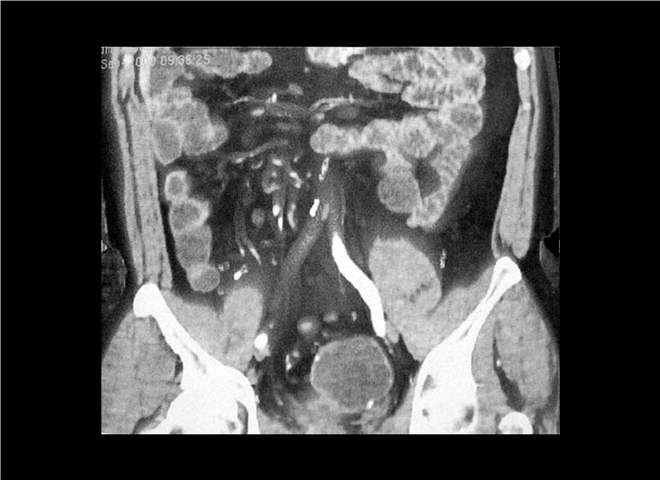

13_CT增强扫描